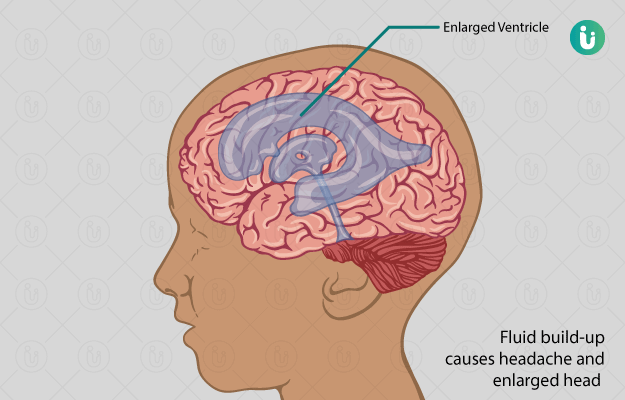

Brain infection causes symptoms prevention and treatment from expert in hindi मस त ष क स क रमण ब र न इ फ क शन क लक षण क रण बच व और इल ज onlymyhealth (फाइल का प्रकार jpg)

Brain Infection Causes Symptoms Prevention And Treatment From Expert In Hindi मस त ष क स क रमण ब र न इ फ क शन क लक षण क रण बच व और इल ज Onlymyhealth